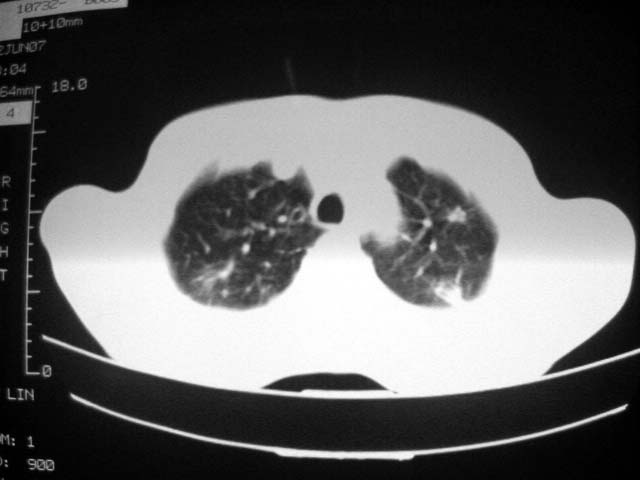

近2个月病灶变化较大,应是感染性病变,首先考虑金黄色葡萄球菌感染。

根据前后片比较应该考虑迁徙性肺脓肿,回帖相差甚远是因为前后片变化太大出乎大家意料之外,这就是影象诊断要结合临床复查对比的必要性,

回顾既往片,病变明显吸收,缩小,未经治疗,不支持肺转移瘤,可能为肺结节病或韦格氏肉芽肿